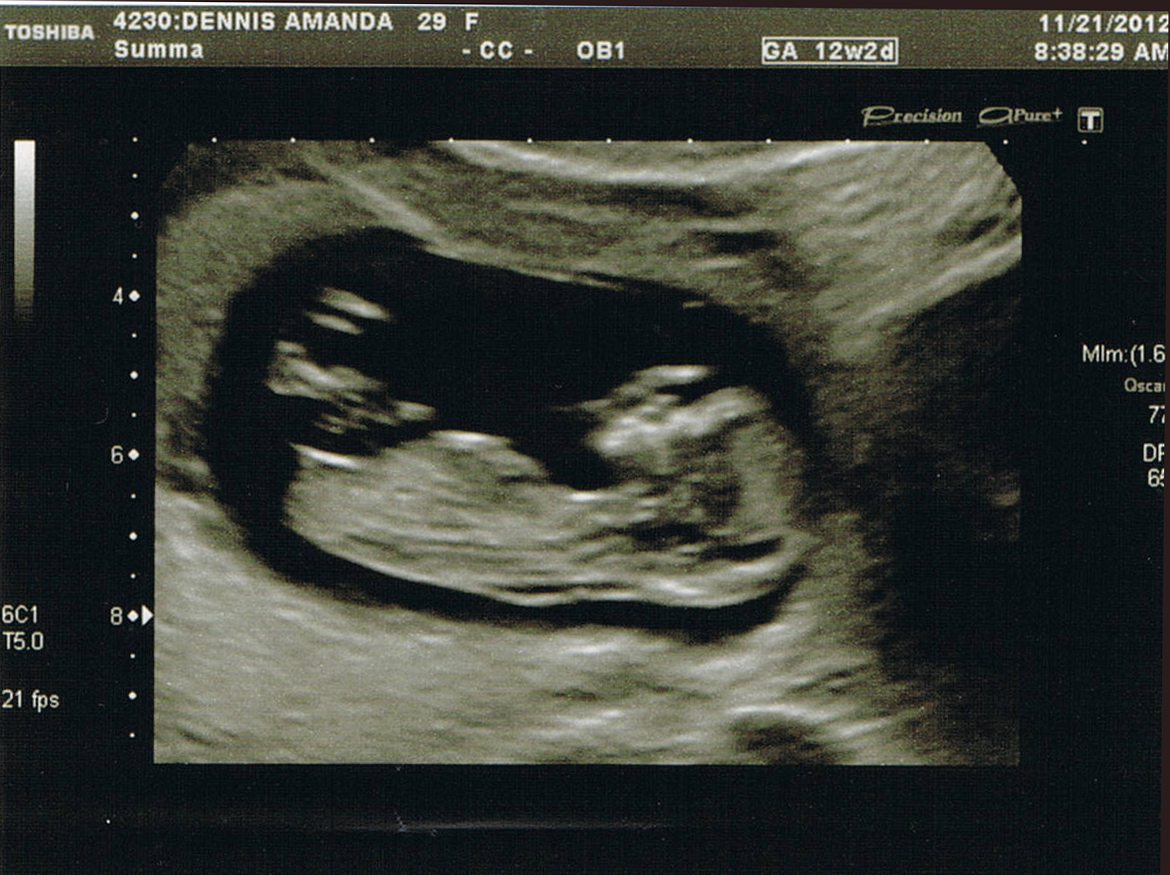

Thank you! Just in case you didn't see my first post, here are the good "nub shots" lol. Thanks again!Attachment 7074Attachment 7075

Second pic looks like my confirmed girl nub. Good luck!